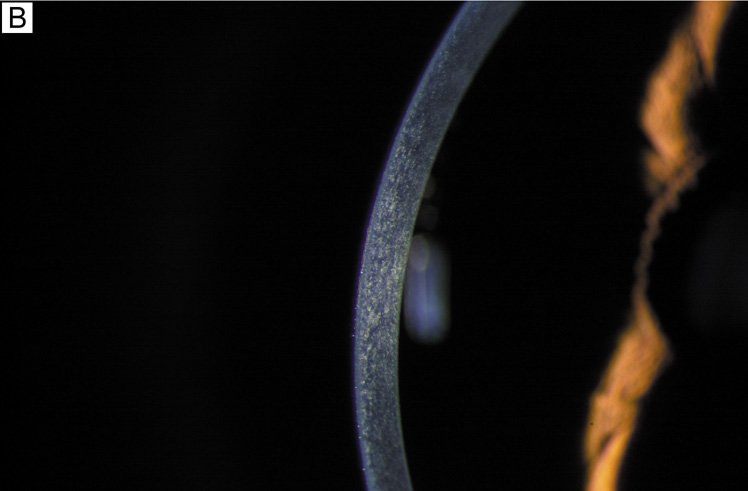

Having a sufficient number of endothelial cells to cover the posterior surface of the cornea along with having integrity of their cell junctions (tight and gap junctions), which are present in the intercellular spaces between endothelial cells, establishes the barrier function of endothelium (Figs. 12 and 22, 23, and 24). Clinically, the barrier function of the cornea can be assessed in vivo by the use of specular microscopy or confocal microscopy (endothelial cell density) or fluorophotometry (permability). In healthy human eyes, this barrier prevents the bulk flow of fluid from the aqueous humor to the corneal stroma, but does allow moderate diffusion of nutrients, water, and other metabolites to cross into the stroma through the 20 nm wide intercellular space. This leaky endothelial barrier may initially seem inefficient, but when one considers that most nutrients for all layers of the cornea come from the aqueous humor, the situation is reasonable.

Fig. 23. Scanning electron micrograph (1,000×) on the posterior surface of the corneal endothelium from a 65-year-old patient with healthy eyes. Note how the hexagonal endothelial cells form a uniform monolayer. Bar = 10 μm.

Fig. 24. Transmission electron micrograph (15,000×) of corneal endothelium from a specimen specially-preserved (glutaraldehyde + cetylpyridium chloride) and stained (tannic acid) to show the glycocalyx of the endothelium. NBDM, nonbanded Descemet's membrane; E, endothelial cells. Bar = 1 μm.